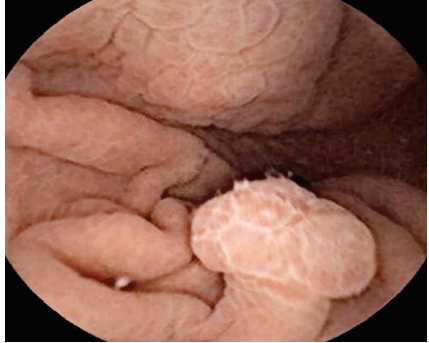

消化内镜检查发现:小星胃内及十二指肠内密密麻麻地长满了大小不等的息肉,部分还有出血及嵌顿肠管内,临床诊断黑斑息肉综合征!

胃肠道息肉

几乎所有的患者都有胃肠道息肉,可分布于全胃肠道,以小肠多见,其次是大肠和胃。这些息肉大小不定,表面光滑,质硬。较大息肉可呈菜花样。